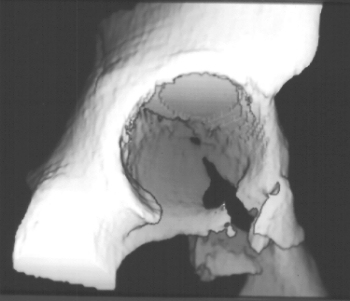

Radiographs revealed a vertical buckle fracture of the right inferior sacrum, oblique fractures of the superior and inferior rami on the right and a fracture through the medial acetabulum. Obturator and iliac oblique inlet and outlet pelvic views, and a thin cut CT with 3-D reconstruction of the acetabulum were performed. These elucidated a comminuted anterior wall with fracture line extending to the posterior column. The posterior column was non-displaced. The pelvic fracture was non-displaced.

1. Right T-shaped acetabular fracture with anterior wall comminution.

COMPUTED TOMOGRAPHY: R/O intra-articular loose fragments, Plan for surgery.